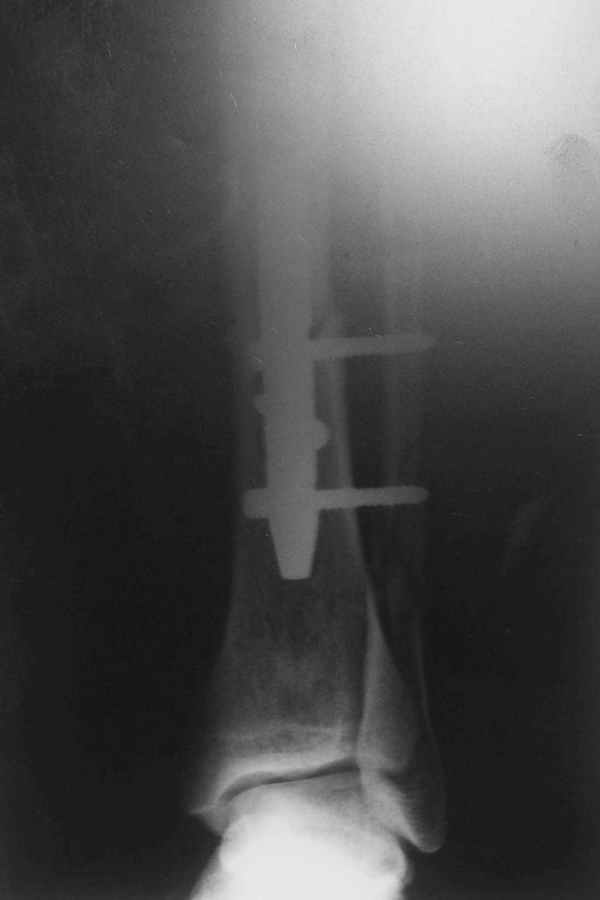

В дистальном отломке три винта( два медио-латеральных и один вентро-дорзальный).

Медио-латеральные вынты - мимо блокирующих отверстий фиксатора, вентро -

дорзальный винт - в отверстии.

Проблемы с верхним дистальным медио - латеральным винтом - он в линии перелома (

перелом косой).

То есть в дистальном отломке всего один запирающий винт. Маловато.

Если в проксимальный отломок стержень сел туго, это не мешает дистальному (широкому и короткому, раз дистальное отверстие уже на уровне перелома) быть нестабильным, особенно если он фиксирован лишь одним винтом.

Выполненный остосинтез нестабилен. Штифт надо заменить по "размеру" на солидный, дистльно три запирающих винта. Успехов!

Перелом спиральный, то есть низкоэнергетический, так что со сращением дело обстоит уже неплохо, лишь бы "костоеда" не развилась. Отломки выглядят уже стабилизированными костной мозолью, так что довводить винты, наверно, уже незачем. Разве что при клинической оценке подвижность еще есть - тогда можно для стабилизации наложить простейший аппарат, не опасаясь контакта его элементов с гвоздем, поскольку места в дистальном метафизе оставлено более чем достаточно.